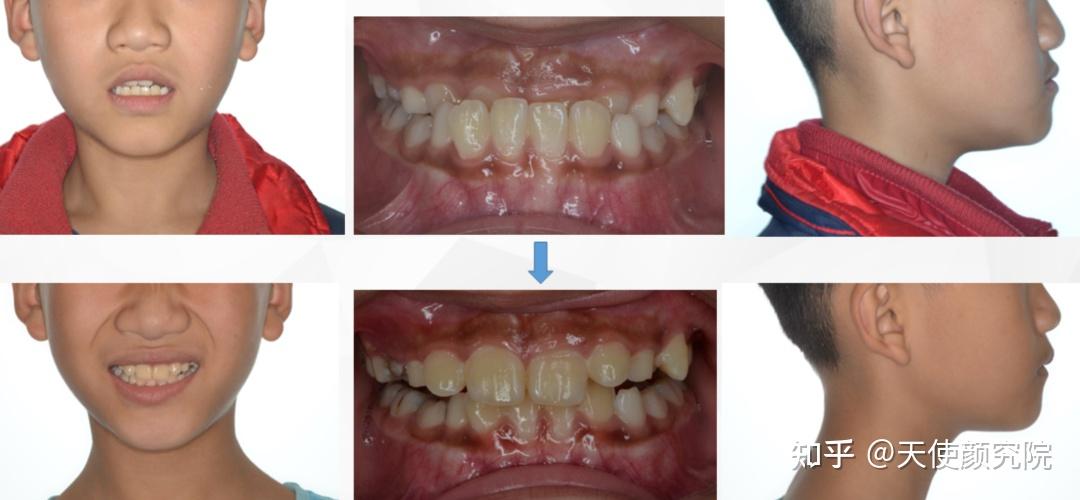

最近突然刷到照片,才惊觉我们的小海丽已经长这么大了,明明感觉没多久前还是奶声奶气的小娃娃呢。

而且,陈智熙(原名)整个人的精致感也随着年龄悄悄增长了。

尤其是小时候有点乱及反颌的牙齿也变整齐啦。